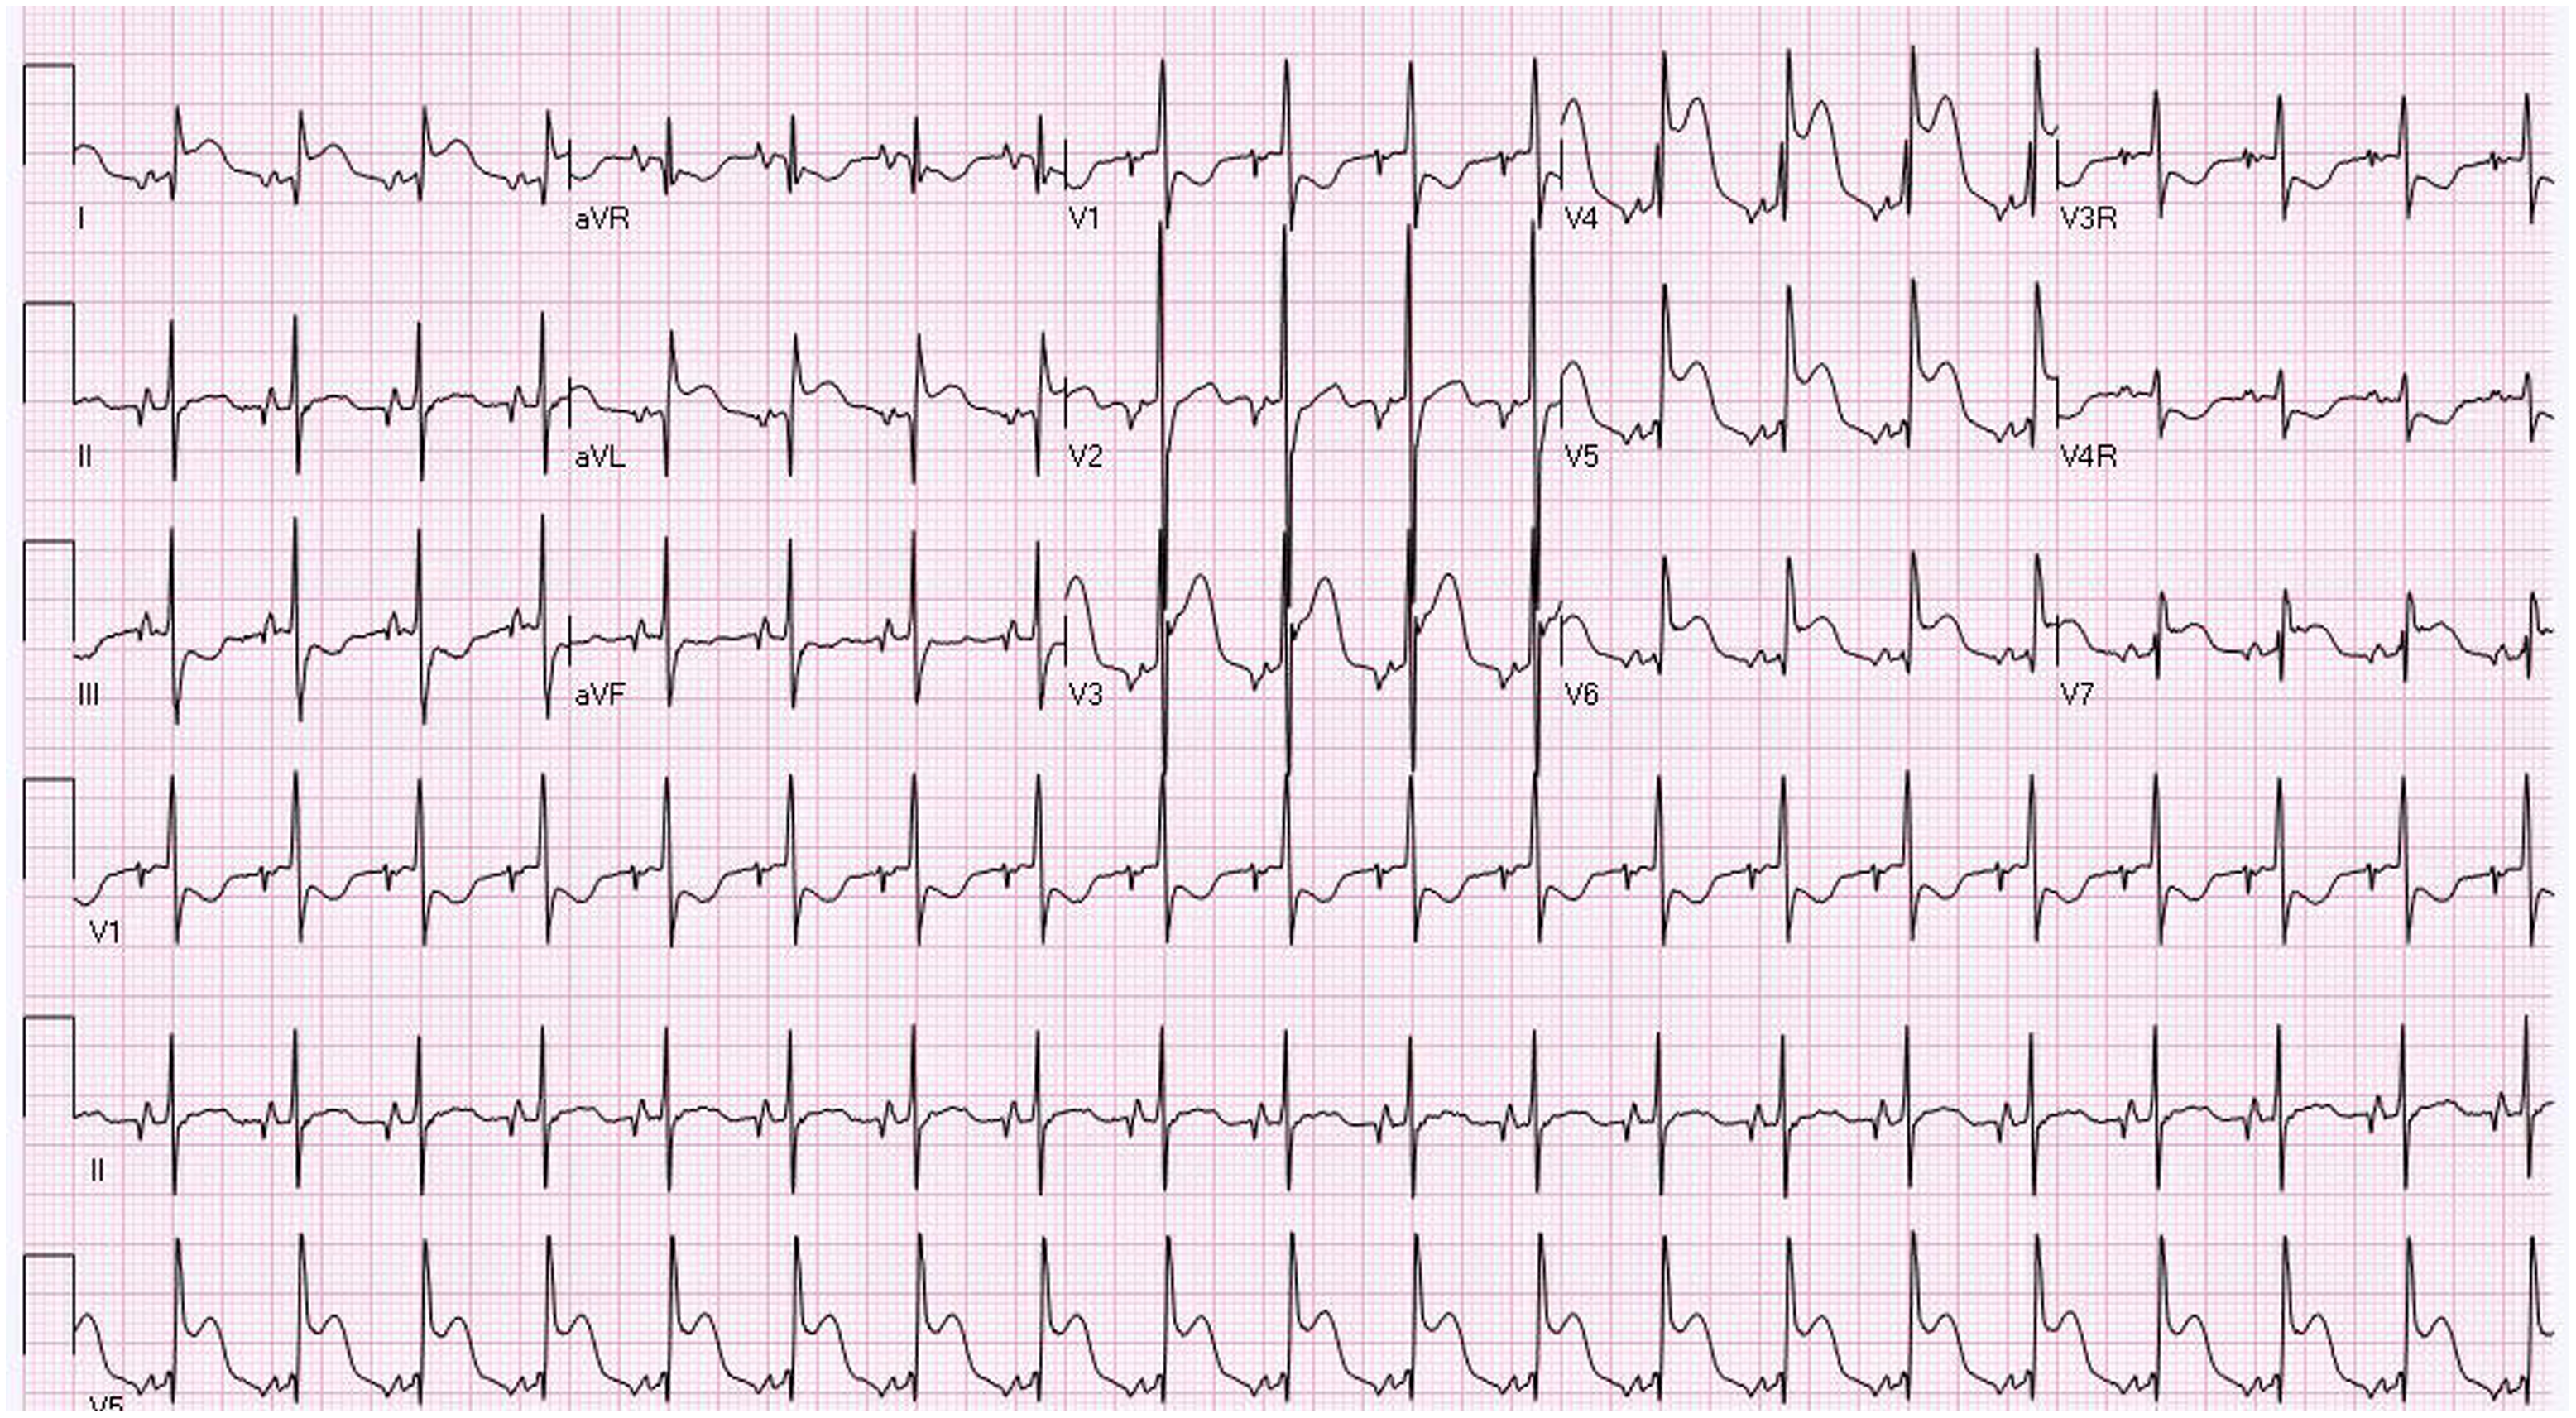

A term male infant was diagnosed postnatally at day 2 after being noted to have tachypnoea which prompted a cardiology workup and was noted to have hypoplastic left heart syndrome with severe mitral and aortic valve stenosis. At 1 week, he underwent Norwood procedure with Sano shunt placement. The Norwood was done with incising down the ascending aorta with side-to-side anastomosis with continuous monofilament sutures with knots on the outside. He had uncomplicated post-operative course and was extubated on post-operative day #5. His initial post-op echo showed unrestrictive atrial septal defect, mild tricuspid regurgitation, patent aortic arch, and Sano shunt with patent Damus–Kaye–Stansel anastomosis with no thrombus noted (Fig 1). On post-operative day #9, he was noted to have sudden onset clinical change after a routine chest physiotherapy and was noted to have sudden onset of bradycardia and hypotension, elevated ST segments with low cerebral and somatic Near Infra-Red Spectroscopy, and elevated blood lactate. A 15 Lead electrocardiogram showed ST elevation (Fig 2). His native aortic root measured around 5 mm and the ascending aorta was 4 mm. The sinotubular junction of the native aortic root measured around 4 mm. An echocardiogram showed a large thrombus (around 5 × 3.5 mm) in his aortic root occluding blood flow into the left main coronary artery (Fig 3a). His labs showed elevated troponins with an initial value of around 14 ng/ml (reference range 0–0.39 ng/ml) which peaked to around 83 ng/ml within 24 hours, with resolution over a week. The patient was intubated, started on low dose epinephrine, and sedated and paralyzed with improved haemodynamics. Haematology was consulted and the patient was started on low dose tissue plasminogen activator at around 0.06 mg/kg/hour, which was titrated to around 0.08 mg/kg/hour based on clot size. Repeat echocardiogram imaging over the next few days revealed decreasing clot size and eventual resolution of thrombus with adequate perfusion of coronary arteries after 72 hours of thrombolysis treatment (Fig 3b).

Figure 2. 12 Lead EKG showing evidence of ST elevation in Lead I, AVL, and V4-V6.

In our patient, clinical presentation was manifested as ST segment elevation on EKG reflecting ischaemia with elevated troponins. Other previous cases reported in the literature Reference Janssen, Ohmstede, Liske, Parra, Drinkwater and Ann1–Reference Brennan, Rodefeld, Tacy, Reddy and Hanley4,Reference Graham, Shakir and Bradley6,Reference Kosaka, Sakamoto, Takigiku, Yasukochi and Harada7 showed patients in age range of 7 days to 4 years who presented with EKG changes like ST depression, T wave inversion, non-sustained ventricular tachycardia, and complete heart block. Some patients had symptoms of chest pain, and most patients were noted to have elevated biomarkers such as troponin. Some patients with native aortic root thrombus did show evidence of ventricular dysfunction. Most patients were diagnosed with transthoracic echocardiography with one patient diagnosed with cardiac catheterisation. Routine evaluation of the aortic root in all patients who present with new sudden onset RV dysfunction should be done to screen for a possible thrombus in the native aortic root with assessment of coronary flow on echocardiogram. Cardiac catheterisation or advanced imaging should be done in cases with clinical evidence of ischaemia but poor echocardiographic windows or concern for thrombus in coronary arterial system which cannot be assessed with transthoracic echocardiogram.